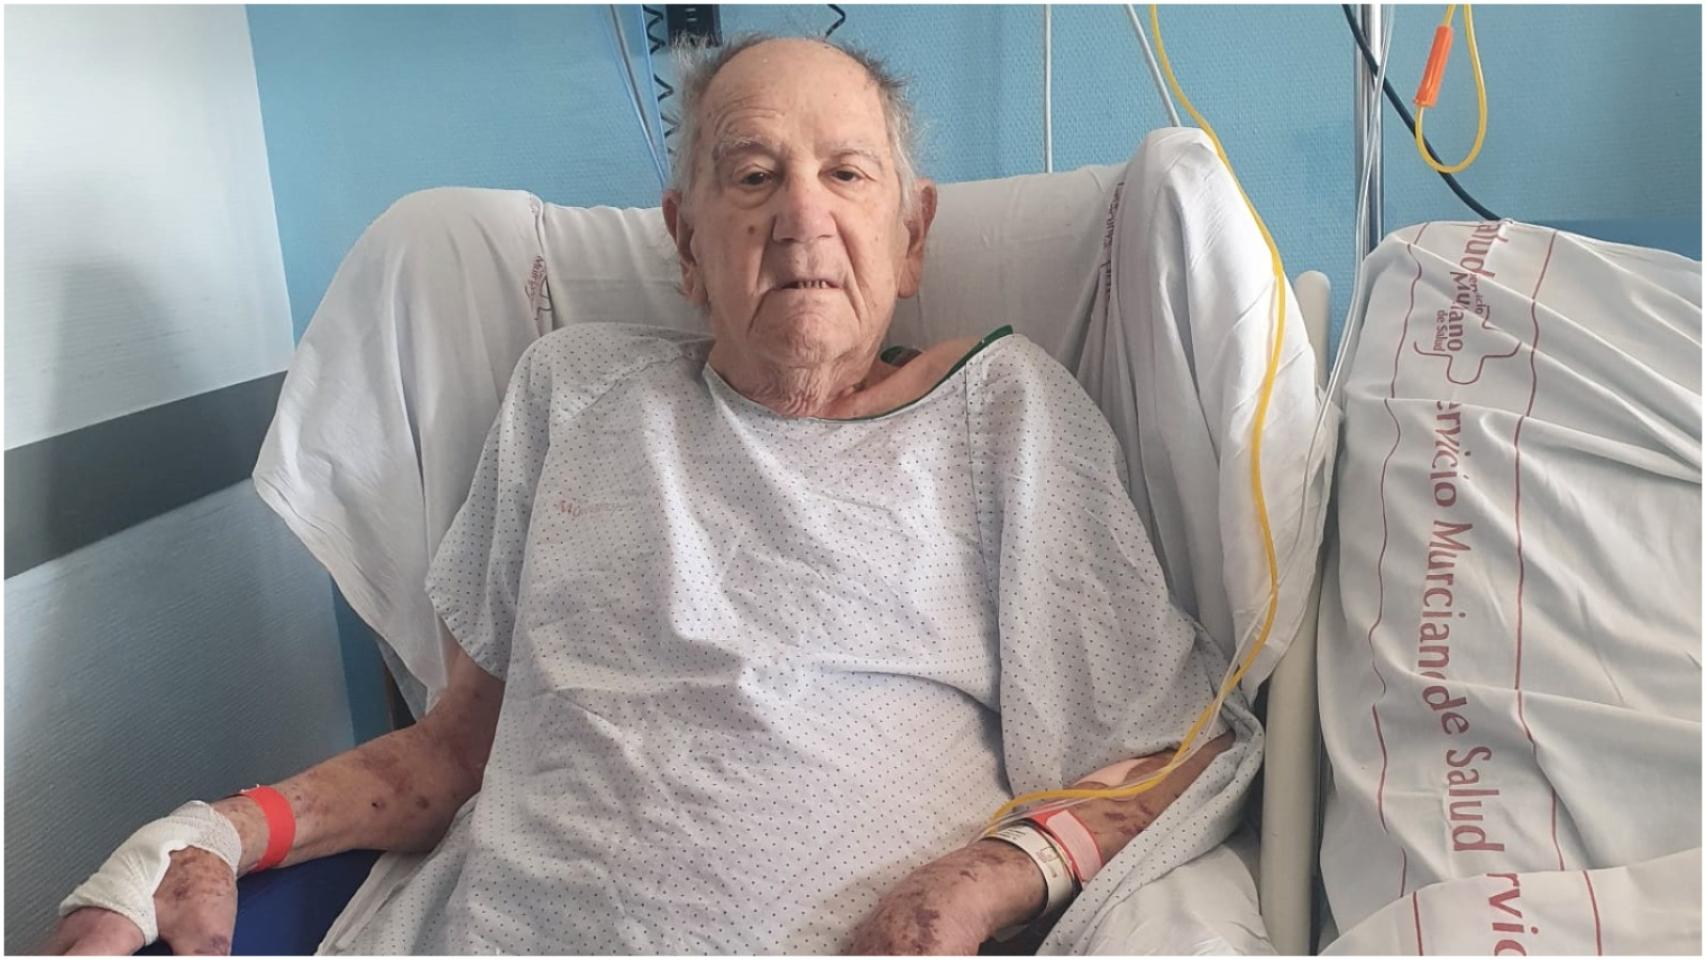

Eva María "sospecha" que su padre está entre los 378 pacientes que la UDEF estima que podrían estar afectados por la trama y pide que investiguen s...